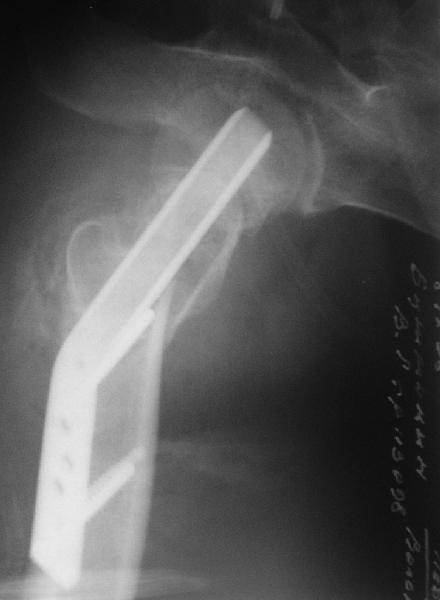

мое мнение может возраст еще позволить чем протезировать, я за остеотомию и синтез. только чем будешь фиксировать если первый вариант выберешь, мне кажется лучше ДХС, только я диафизарную часть пластины разгибаю под углом вальгуса, обычно заранее. недавно я тоже делал такой же случай, но там он был моложе. Ерсин. Астана

Приветствую всех. Спасибо за активное участие в обсуждении. Выбрали вариант с остеотомией.

Снимки в приложении.